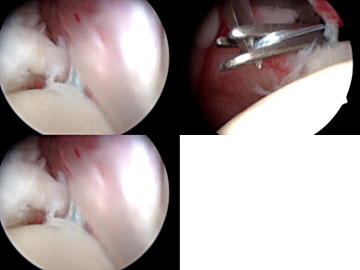

Arthroskopische

Rotatorenmanschettennaht

Die Technik der arthroskopischen RM-Naht hat sich in den letzten

Jahren durch die Einführung von endoskopischen Nahtinstrumenten,

Nahtzangen und Schraubankern deutlich verbessert. Während vor

einigen Jahren meist nur einreihig genäht wurde, ist heute

das Ziel die Ansatzfläche der Sehnen an ihren Anheftungsstellen

(Foot print) großflächig wiederherzustellen. Diesbezüglich

werden heute zweireihige Nähte vorgenommen. Schwierig, aber

technisch machbar ist die arthroskopische Rekonstruktion der Subscapularissehnenausrisse.

|

Abbildung:

Endoskopische Subscapularissehnenaht |

Endoskopische Supraspinatussehennaht |